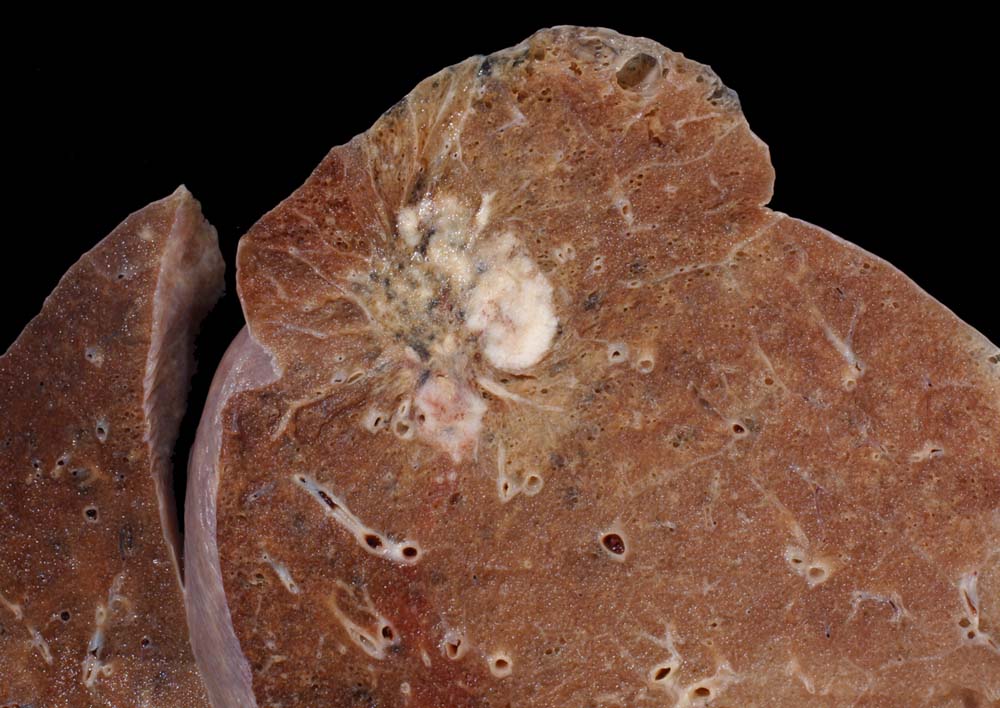

Makroskopie

Befund

Pathologischer Befund

Normalbefund